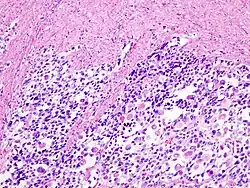

Le carcinosarcome est une tumeur maligne associant des aspects carcinomateux et sarcomateux[1]. Il est fréquemment de localisation utérine.